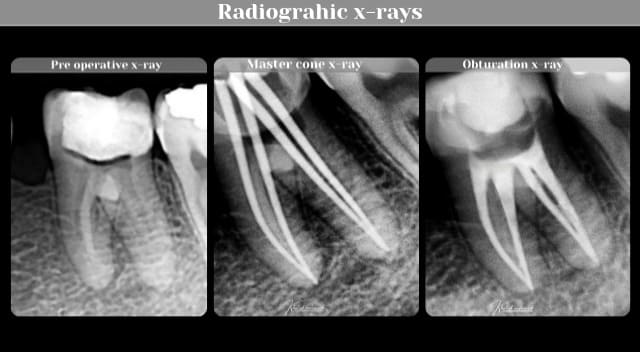

Pre operative x-ray

Master cone x-ray

Obturation x-ray

RCT x-rays collection